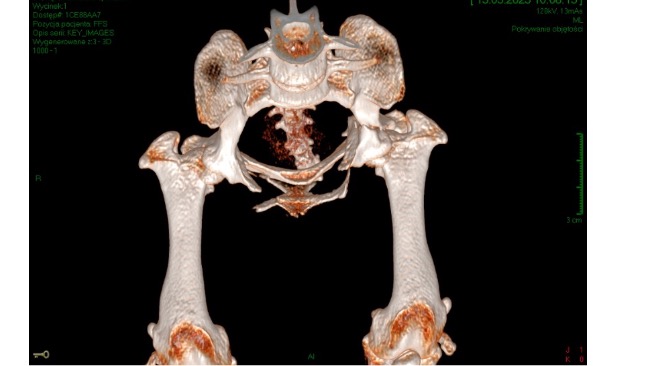

U Czarusia doszło do poważnego złamania kości w obrębie miednicy - złamanie kości łonowej, kulszowej, panewki lewego stawu biodrowego oraz pęknięcie lewej kości udowej, a także pęknięcia kości w stawie łokciowym lewej przedniej łapki.

Psiak został skierowany do specjalistycznej kliniki ortopedycznej. Po konsultacji chirurgicznej u cudownego lekarza z kliniki Dr Hau w Krakowie (koszt konsultacji wraz z badaniem RTG to 1 100 zł) oraz wykonaniu serii badań, w tym tomografu komputerowego, którego koszt przekroczył 2 000 zł, niezbędna okazała się pilna operacja złamanej kości biodrowej i kulszowej - Czaruś ma założoną płytę panewkową wraz z wkrętami kostnymi (koszt zabiegu to 4 590 zł). W kolejny poniedziałek przeszedł drugą operacja ortopedyczna polegająca na złożeniu kości stawu lewej przedniej łapki (założono śrubę). Czarusia czekają regularne wizyty kontrolne, zmiany opatrunków, wymiany cewnika, a później kosztowna rehabilitacja.